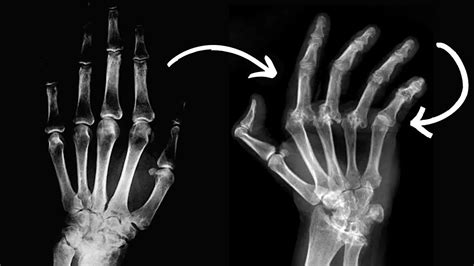

Ilustración de las articulaciones afectadas por artritis en las manos

• Artritis Reumatoide (AR): Una enfermedad autoinmune donde el sistema inmunológico ataca erróneamente el revestimiento de las articulaciones (sinovial), provocando inflamación crónica, dolor intenso y, si no se trata, deformidades articulares.

• Deformidades o bultos: Aparición de nódulos óseos (nódulos de Heberden o Bouchard) en los dedos o desviación articular.